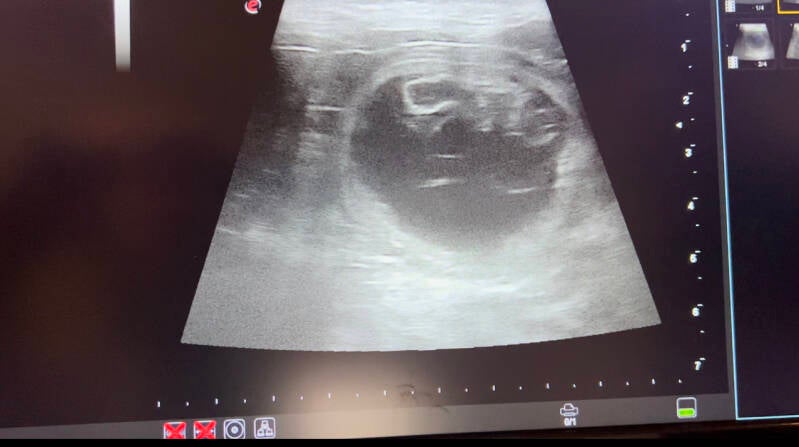

Dan is het toch gelukt Stitch is drachtig!! En wat zijn we blij dan begint de voorzichtige telling van de embryo's en komen we voor nu op 7, omdat ik geen stress bij haar wil besloten om haar niet te laten liggen dus misschien is het er eentje meer. Maar voor nu maakt dat niet uit op 2 mei gaan we voor de laatste telling!

2 mei ongeveer een week voor de bevalling hebben we deze foto's laten maken, Omdat haar buik zo groot is zijn ze niet echt duidelijk maar samen met de dierenarts tellen we er nu 8.